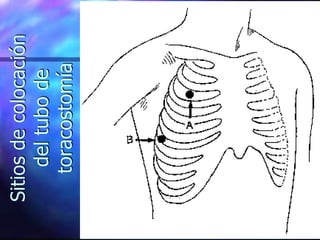

TECNICA DE DRENAJE TORAXICO

Sitios

de

colocación

del

tubo

toracostomía

http://es.youtube.com/watch?v=y_QeukoK5Dw